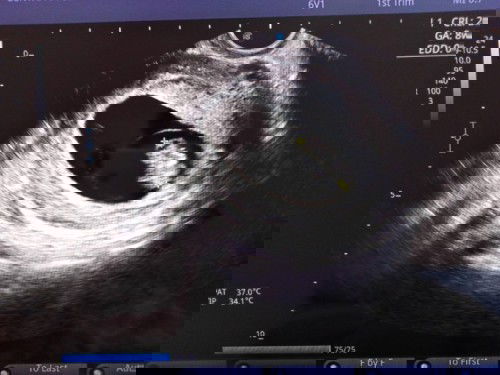

เย้ๆๆ เจอหัวใจน้องแล้ว คร้าาา ❤️❤️❤️

#อัพเดท คร้า หลังจากที่ไปซาว ตอน 5 week หมอบอกน้องตัวเล็กมากๆ เมื่อวันที่ 24 ม.ค 😊ที่ผ่านมา หมอนัดไปซาวอีกครั้ง วันนี้ได้เจอน้องแล้วคะ น้องหัวใจเต้นแล้ว ❤️ได้ฟังเสียงหัวใจของน้อง ละขนาดตัวของน้อง สมบูรณ์ ตามเกณฑ์ ดีแล้วคะ😊😊 คุณหมอนับ week ใหม่จากขนาดของน้อง 2 cm. คุณหมอบอกว่าน้อง 8week 4day คะ คุณหมอนัดฉีดยากันแท้งทุกสัปดาห์เพราะแม่มีประวัติแท้งมา2ท้อง 😶แล้วคะ ครั้งนี้ได้มุดสีชมพู 💗อีกครั้ง พร้อมภาพซาว ของน้อง 🎉🎉 คุณพ่อยิ้มไม่หยุดเลยจ้า 😍😍#ท้องแรกคะ #คุณแม่ๆช่วยแนะนำหน่อยค่ะ